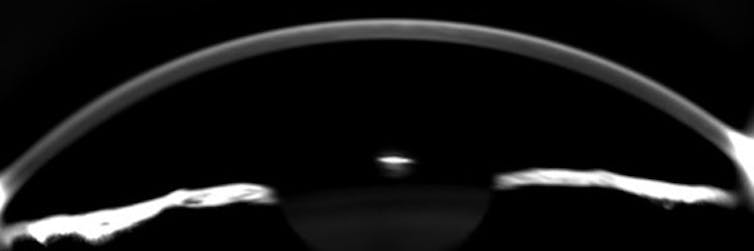

La córnea es un órgano vital en la visión. Se trata de un tejido complejo avascular delimitado por dos epitelios: el anterior (que interacciona con la lágrima y permite la regeneración y cicatrización) y el posterior o endotelio (que permite el paso de nutrientes).

Su particular estructura permite que el tejido corneal sea transparente y que la luz se transmita de forma correcta en el espectro visible (entre 380 y 780 nanómetros). En caso de alterarse dicha transparencia (así sucede en procesos inflamatorios como el edema, quemaduras o heridas), la córnea se vuelve opaca, lo que genera visión nebulosa.

Por otro lado, los radios de curvatura e índice de refracción corneales permiten focalizar la luz procedente de los objetos sobre el campo angular retiniano. Si, por diferentes motivos, estos parámetros son alterados, el sujeto experimentará fenómenos de desenfoque (miopía e hipermetropía) o astigmatismo.

Otra función primordial de esta parte del ojo es la de compensar la presión intraocular. Por una parte, permite mantener la forma del globo ocular, además de absorber la energía transferida mediante presión externa o interna al órgano visual. De esta forma, se preserva la estabilidad del tejido y, por consiguiente, el resto del globo ocular.

Podría decirse que una córnea sana ejerce la función de amortiguador en el ojo, absorbiendo las fluctuaciones de la presión intraocular y evitando así un daño paulatino en el nervio óptico. Esta propiedad fundamental se debe a su carácter viscoelástico; es decir, el tejido corneal recupera su forma original tras el cese de una presión externa, pero lo hace de una manera lenta y progresiva.